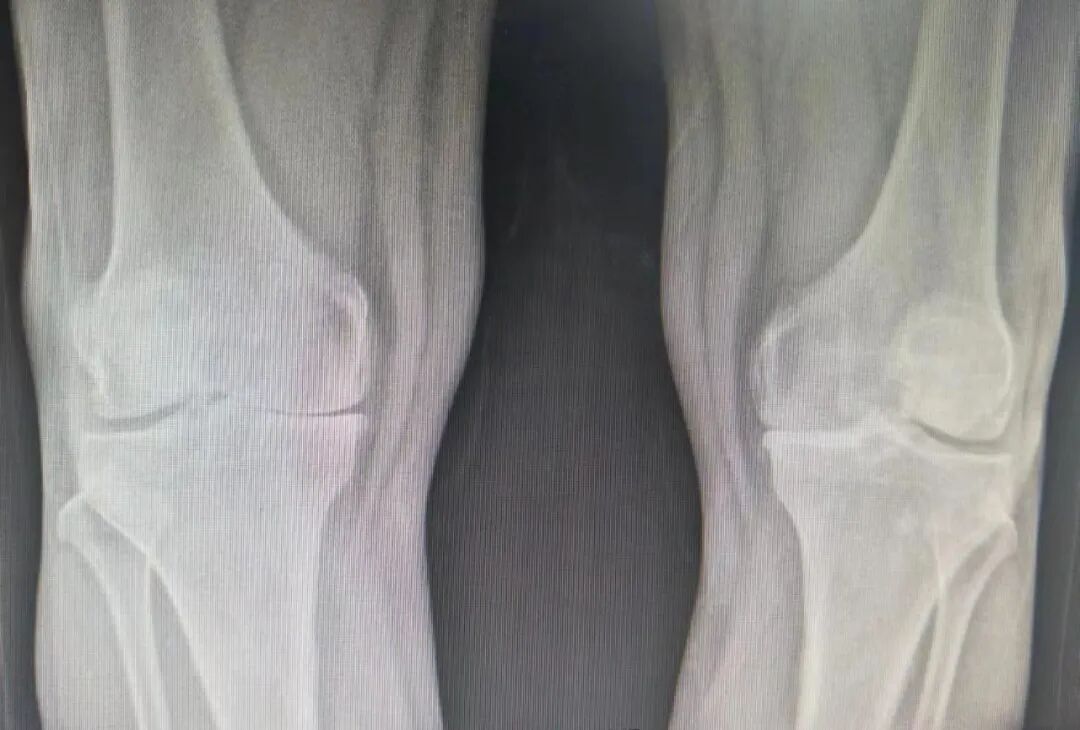

59岁刘某,以”双膝关节疼痛伴活动受限3年”主诉入院。入院诊断:双膝骨性关节炎;骨质疏松症。骨科鞠主任为患者行双膝人工关节表面置换术,其中使用骨科高值耗材费用从集采前的4.5万元左右,降到了集采后的9300元左右,患者在来院之前了解到需花费近5万余元,如今使用国家集采后的耗材,让患者家属对国家骨科耗材集采的好政策赞叹不已。

患者术前